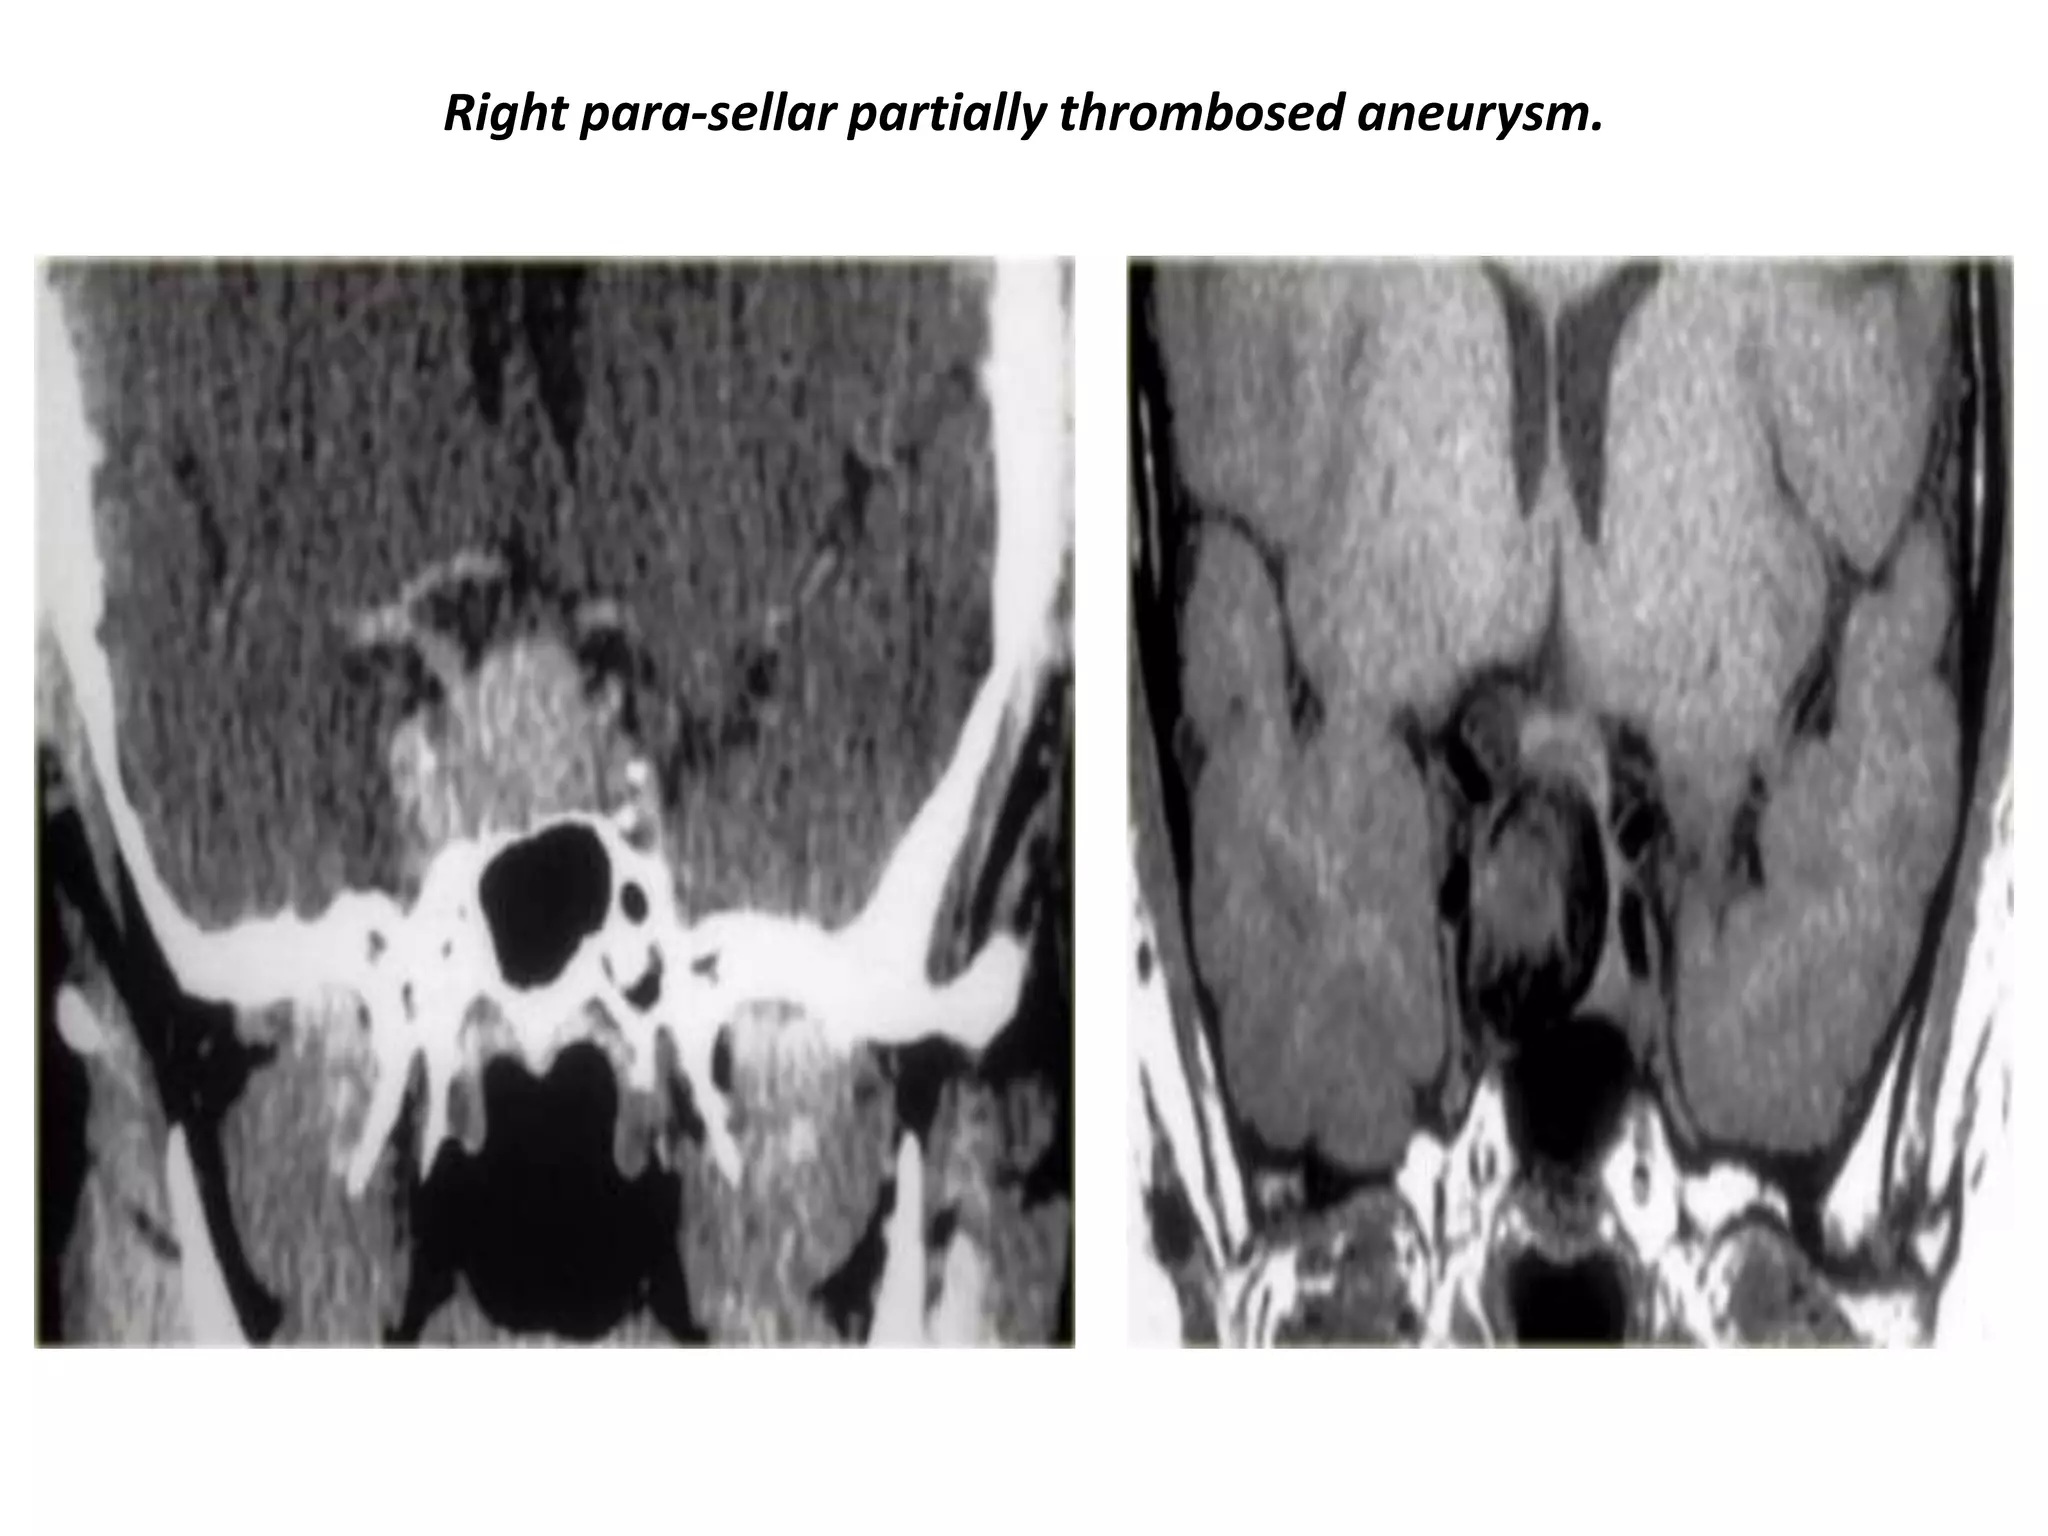

Right para-sellar partially thrombosed aneurysm.

Aneurysm of right para-sellar region with partially thrombosed aneurysm.

Enhanced and non-enhanced study of right para-sellar aneurysm.

The mass is predominantly black and there is a large flow artifact running in the phase-encoding direction.

These findings correspond to rapid blood flow, and the mass must therefore be an aneurysm